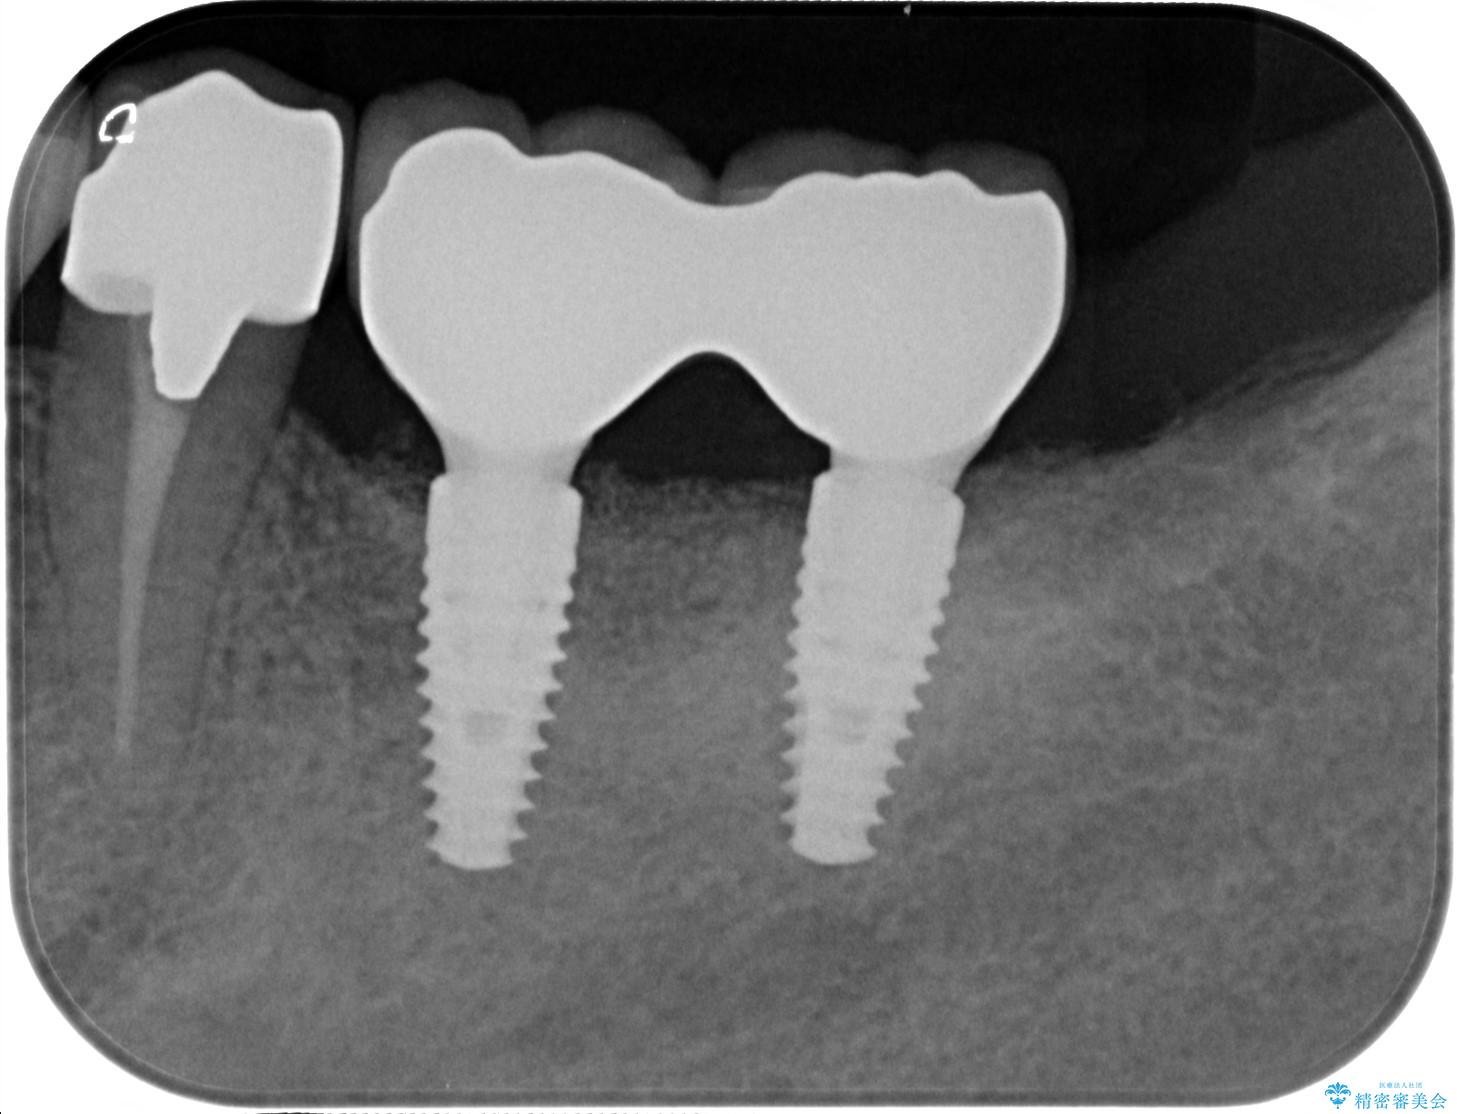

遊離歯肉移植術を併用した、破折歯のインプラント治療

抜歯後、インプラントを用いて咬合機能を回復すると共に周囲に強固な角化歯肉を移植することによりより長期にわたり安定したインプラント周囲環境となるよう治療を計画します。

- 83.6万円(インプラント×2・アバットメント×2・クラウン×2)費用は治療当時の料金となります

インプラント周囲の角化歯肉が存在することにより、歯ブラシがしやすくなりインプラントにトラブルが起きる確率を減らしより長期的な予後を望むことができます。